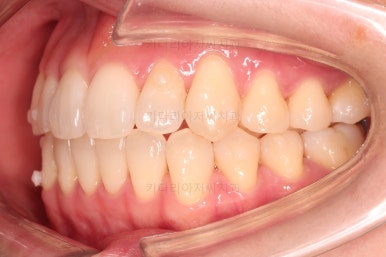

1. 초진

초진 시 입안의 모습입니다.

덧니가 눈에 띄고요.

맞물림이 긴밀하지 못한 상태였습니다.

전반적으로 약간 삐뚤지만 많이 심하다고 보긴 힘들었습니다.

덧니가 있는 방향으로 치열들이 쏠리고 틀어져 중앙선이 맞지 않는 양상이었습니다.